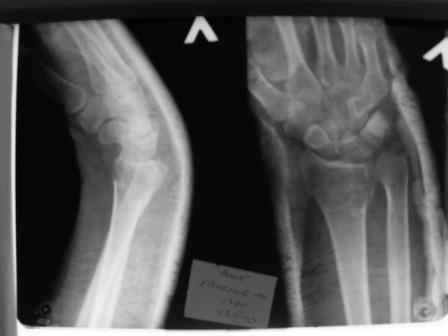

Уважаемые коллеги.Прошу обсудить случай лечения перелома дистального метаэпифиза лучевой кости. Ситуация скандальная и крайне неблагоприятная. Больная с патологической обстоятельностью мышления, склонностью к сутяжничеству, патологическими умозаключениями, не поддающимися коррекции (см. психиатрию, правда офиц. диагноза нет). В данном случае есть ряд ошибок с нашей стороны, прежде всего в отношении качества ведения документации (за что получил административное взыскание, по делом мне дураку). В остальном- придерживались в лечении подхода классический советской школы. Так как умную операцию…… сами знаете… 15.12- перелом луча в Москве. Там же репозиция, гипс. Дальнейшее лечение у нас в ЦРБ. 20.12.- вторичное смещение в гипсе21.12- под внутривенным наркозом- репозиция, гипсовая лонгета. Дальше начинается самое интересное. После репозиции больная заявила, что я (репозицию делал я) порвал ей все связки в суставе, посинел у нее 5 палец, якобы я за него тянул и т. д. На самом деле на 2 сутки после репозиции рука немного отекла и было незначительное сдавление гипсом, который был ослаблен. Дальнейшее лечение консервативное. Через 6 недель- гипс снят, назначено ЛФК. Пациентка крайне недовольна. Говорит, что на снимке у нее выступает кость, я ей сломал руку и.т.д. В общем началось. Пациентка прочитала в интернете наверное все, что есть по данной травме.По заключениями рентгенологов и консультанта из КДЦ областной больницы - стояние отломков допустимое. Объективно говоря- снижена высота лучевой кости, диастаз лучелоктевого сочленения, и не сросся шиловидный отросток. однако на РКТ при сравнении с другой стороной- разница незначительная. Дальше в одной из больниц нашей области и одной из больниц Москвы (вроде бы КГБ 53) врачи сказали, что репозиция сделана плохо. Нужна операция (восстановить длину лучевой кости), даже один из них предложил РЕДРЕССАЦИЮ (хи-хи) с наложением аппарата Илизарова. Что это для данной больной- радость неописанная. (см. описание психического статуса). Ничем другим, кроме зарабатывания дешевого авторитета объяснить данный факт не могу.Кстати, у больной еще нейропатия локтевого нерва.Для разрешения конфликта больная направлена на консультацию в ЦИТО на 03.03.11.

1. РЕПОЗИЦИЯ сделана качественно(ОСНОВНЫЕ 2 УГЛА ВЫСТАВЛЕНЫ ПРАВИЛЬНО ) , но перелом нестабильный и склонен к втор смещению . Поэтому мы стараемся все переломы со смещением фиксировать 3-МЯ спицами по GRIN методике .

1. Репозиция от 21.12.10 была выполнена лучше, чем первичная.

2. Укорочение лучевой кости с изменениями дистального лучелоктевого сустава требует оперативного лечения

Заключение: Консолидированный в неправильном положении перелом дистального метафиза левой лучевой кости. Ротационная контрактура левого предплечья. Рекомендовано- разработка, консультация через 2 месяца.